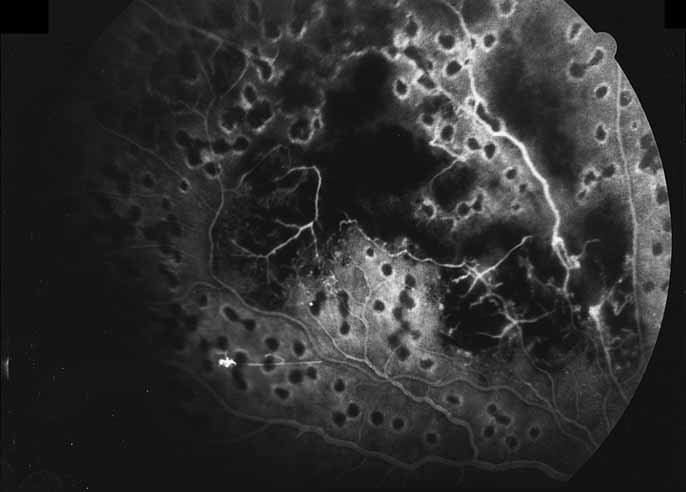

Fig. 10 Acute multifocal hemorrhagic retinal vasculitis. A middle-aged man presented with the picture of multiple branch vein obstructions and low-grade intraocular inflammation.

Fig. 11 Acute multifocal hemorrhagic retinal vasculitis. Fluorescein angiogram confirms the presence of associated retinal capillary non-perfusion without neovascularization at the onset of the disease.